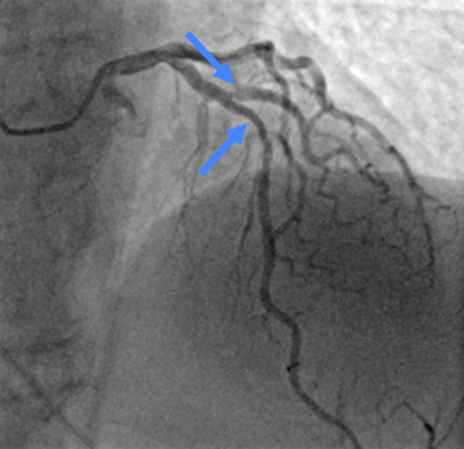

Пациентка П., 72 лет была госпитализирована в Больницу 52 в плановом порядке с клиникой стенокардии напряжения. В прошлую госпитализацию пациентке выполнялось ЧКВ со стентированием диагональной артерии при ОКС с подъемом с ST. В тот момент стеноз в передней межжелудочковой артерии (ПМЖА) был расценен оператором как пограничный и требующий дообследования, была выполнена реканализация, баллонная ангиопластика и стентирование инфаркт-ответственной диагональной артерии (ДА). В настоящую госпитализацию при коронарографии у пациентки визуализируется стеноз в ПМЖА 70%, также был выявлен стеноз в устье ДА перед ранее имплантированным стентом до 80%. Перед коронароангиографией пациентке был выполнен нагрузочный тест: тест незавершенный. В операционной с целью определения гемодинамической значимости стенозов ПМЖА и ДА было выполнено определение моментального резерва кровотока (МРК) в ПЖМА и ДА. Значение МРК в ПМЖА 0,84; в ДА — 0,95. Таким образом, поражение в ПМЖА являлось гемодинамически значимым и требовало стентирования, а поражение в ДА — нет.